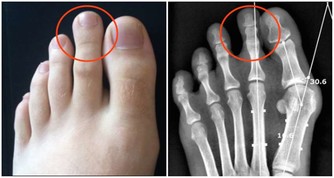

靜脈曲張

隨著肝硬化的進展,可出現不同程度的腹壁靜脈曲張,以臍為中心,周圍淺靜脈突起擴張,形似蚯蚓狀,向四周放射性分佈,以上腹壁多見。